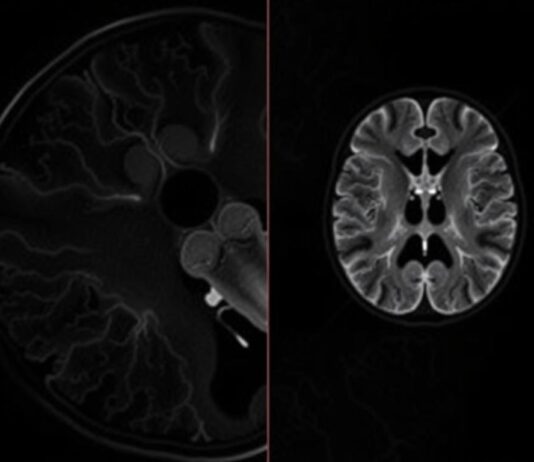

МРТ-ангиография: невидимая карта ваших сосудов, которую может сделать только магнит

МРТ-ангиография — это способ заглянуть внутрь сосудистой системы без скальпеля и без лучевой нагрузки. Она дает трёхмерную, детальную картину артерий и вен, помогает понять,...